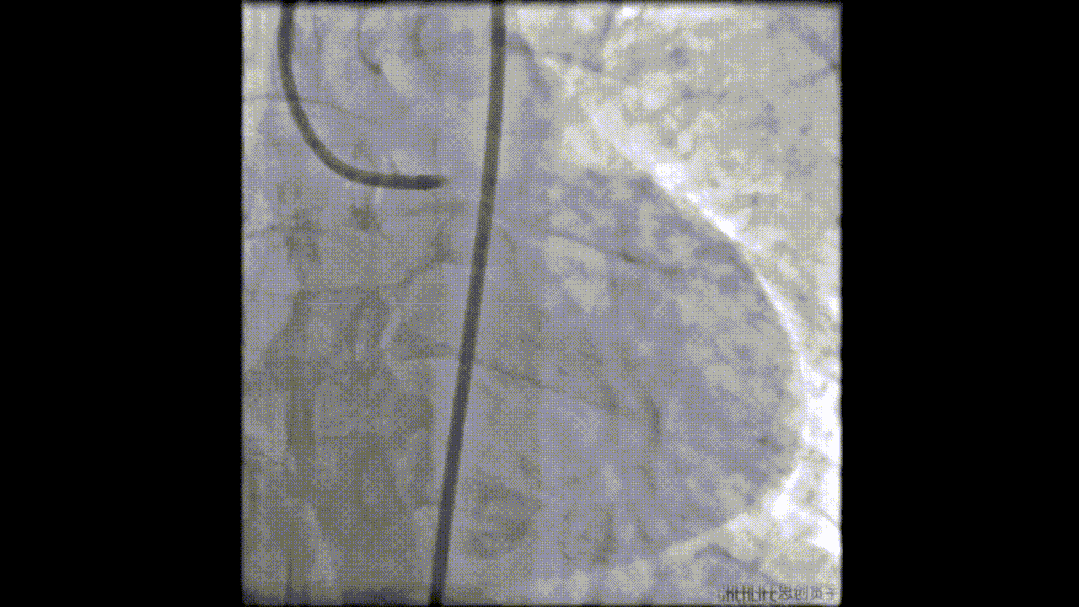

术后造影图像